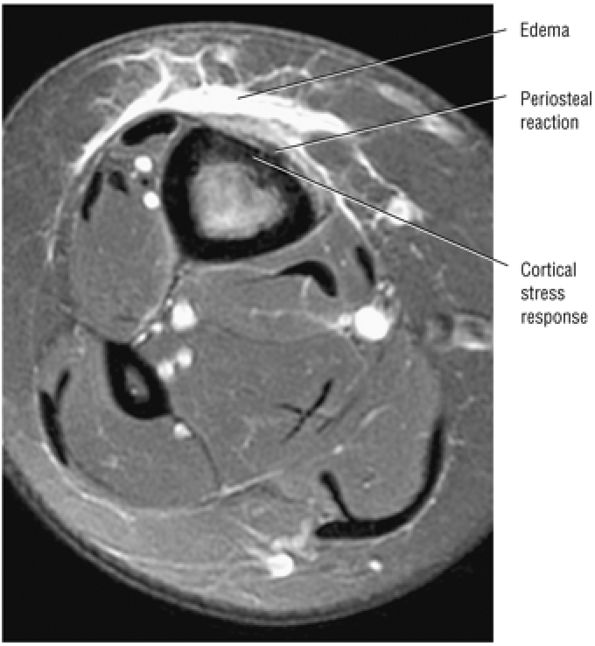

Stage I: Subchondral trabecular compression. Radiograph results are negative, bone scans are posi-tive, and marrow edema is seen on MR imaging (Fig. 5.95).

-